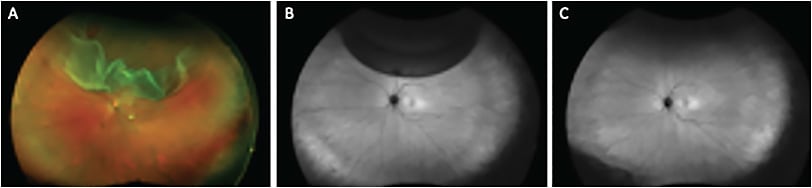

There is also emerging evidence that the integrity of retinal reattachment varies with the surgical technique chosen. A recent study demonstrated that PnR was associated with a greater chance of achieving a high integrity retinal attachment (HIRA) compared with PPV.2 This may be related to several factors, but particularly that PnR is an RPE pump-based procedure where the gas bubble occludes the retinal break and the RPE pump is responsible for slowly achieving retinal reattachment. Furthermore, PnR utilizes a smaller gas bubble, which applies less buoyant force to a smaller area of retina, thereby increasing the chance of HIRA. To the contrary, PPV is associated with a rapid iatrogenic process of retinal reattachment in which fluid is manually removed from the subretinal space over a short period of time. Moreover, large gas fills are used with a large buoyant force applied to a large area of retina, which likely leads to a high risk of retinal displacement or a low integrity retinal attachment (LIRA) (Figure 1).